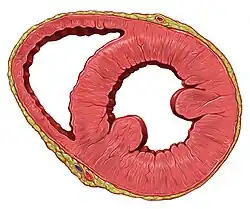

Coupe frontale du ventricule gauche du cœur humain.

Coupe frontale du ventricule gauche du cœur humain. Les principales parties du cœur.

Elle est essentiellement constituée pour les deux tiers de sa surface par la paroi du ventricule gauche. Le tiers droit est formé par la paroi du ventricule droit. Ces deux parties étant séparées par le sillon interventriculaire postérieur.

Tissu contractile

Le tissu contractile constitue la masse principale du cœur et permet sa contraction. Il s'agit du myocarde, un type de tissu musculaire strié spécifique au cœur. Ce tissu est constitué de cardiomyocytes, cellules spécifiques mesurant 120 μm de long et 20 à 30 μm de diamètre chez l'adulte. Ces cellules contiennent un[5] ou deux noyaux en leur centre, de nombreuses mitochondries et surtout des myofibrilles agencées de manière linéaire et qui constituent la majeure partie de ces cellules. Les extrémités des cardiomyocytes sont divisées en plusieurs branches anastomosées avec plusieurs autres cellules, ce qui forme un réseau complexe de cardiomyocytes en continuité. Ces cellules sont entourées de tissu conjonctif, l'endomysium, et sont regroupées en travées également entourées de tissu conjonctif, l'épimysium. Le myocarde est situé principalement dans les parois du ventricule gauche, mais il est présent dans toutes les autres parois. Il n'est pas retrouvé au niveau des valves. Les cardiomyocytes atriaux sont de plus petite taille et contiennent en outre des granules. Ce tissu contractile myocardique a des propriétés viscoélastiques : mécaniquement, si on l'étire, il reviendra a sa taille/forme d'origine.